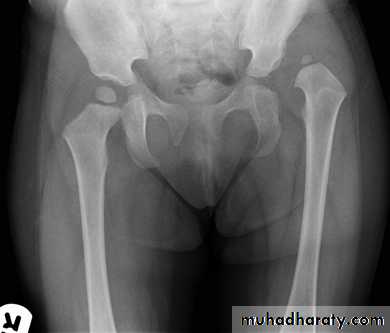

DEVELOPMENTAL DYSFLASIA OF HIP (CONGENITAL DISLOCATION OF THE HIP)

• An abnormally lax joint capsule allows the femoral head to fall out of the acetabulum, leading to deformation.• Predisposing factors for the development of CDH are:

• * Abnormal ligamentous laxity (effect of estrogen; fema1e:male = 6:l)

• * Acetabular dysplasia .

• CDH occurs most commonly (70%) in the left hip. Bilateral involvement is seen in 5%.

• Radiographic features

• US (commonly used today) at 1-3 months

• * Normal femoral head is covered at least 50% by acetabulum , In CDH < 50% of femoral head is covered by acetabulum .

Plain film

At 3-6 months :By doing special veiw (Von Rosen veiw )by abduction of the thigh 45 degree and internal rotation .

In DDH the lines that drown through the femura will meet in higher level than the normally should at lumbosacral joint .

6 months and later

* AP veiw ( femural epiphysis are visualized ):* Superolateral displacement of proximal femur (disturbed shenton’s line )

* Increase in acetabular angle

* Small capital femoral epiphysis

Femoral head is located lateral to Perkin's line

* Other features that are sometimes present

Abnormal sclerosis of the acetabulum

Shallow acetabulum

Formation of a false acetabulurn

Delayed ossification of femoral head